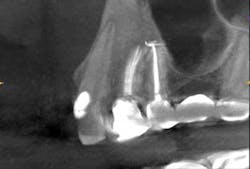

Ten days later, the patient returned asymptomatic. Again, after proper anesthesia and isolation the temp filling was removed, additional irrigation, along with cleaning and shaping of the canals was continued, the case was obturated, and a permanent seal placed that day. The patient reported for a 14-month follow-up and a subsequent CBCT image was obtained (Fig. 7). The sagittal view shows complete boney healing of the previous periapical lesion, and retention of the fixed prosthesis.

Fig. 7: CBCT sagittal view (Nos. 4 and 5) 14-month postop, showing complete resolution of the apical lesion with intact lamina dura